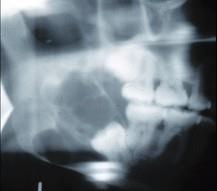

女,32岁,右下后牙龈向外膨隆,后牙渐松动3个月。X线片(如图)示右下颌磨牙区颌骨呈蜂房样改变,病变区牙根呈锯齿状吸收。该病人最可能的诊断是 ( )

A右下颌骨骨肉瘤

B右下颌骨角化囊肿

C右下颌骨成釉细胞瘤

D右下颌骨骨巨细胞瘤

E右下颌骨中央性颌骨癌